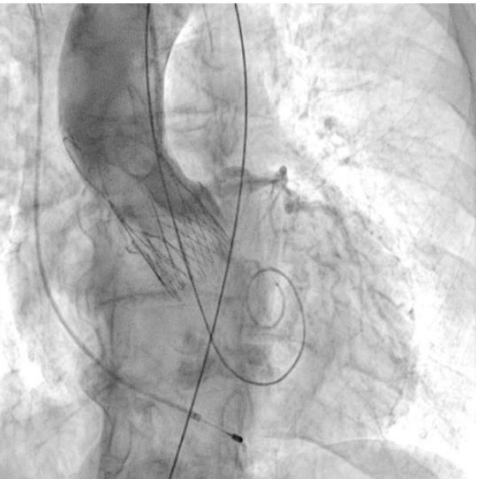

Процедура ТИАК выполнялась по стандартной методике, принятой в нашем центре (рис. 6-9). После предилатации баллонным катетером "Valver" 18×40 мм возникло ухудшение гемодинамики за счет развития выраженной аортальной регургитации, проявившееся снижением диастолического АД до 20 мм рт.ст. В срочном порядке была выполнена имплантация "Acurate Neo2 S" диаметром 23 мм в аортальную позицию, после чего явления гипотонии и сердечной недостаточности были компенсированы. Коронарные артерии не были скомпрометированы. После выполнения основного этапа операции интродьюсер из правой общей бедренной артерии удален, затем выполнено ушивание места доступа системой зашивающего устройства "ProGlide" (6F) и AngioSeal VIP (6F), наложен кожный шов. Ход оперативного лечения без особенностей.

Рис. 6. Пациентка В. Ангиография корня аорты: визуализируется минимальная регургитация.

Рис. 8. Пациентка В. В момент проведения и позиционирования искусственного клапана визуализируется умеренная регургитация.

Рис. 9. Пациентка В. Контрольная ангиография.

В послеоперационном периоде по данным ЭхоКГ нормально функционирующий биологический протез в аортальной позиции. V max — 2,0 см/с, средний градиент — 8,1 мм рт.ст. Парапротезная регургитация минимальная. Динамических изменений на ЭКГ не обнаружено.

Во втором клиническом случае был учтен предыдущий опыт и изменена тактика проведения вмешательства у пациентки с аналогичным фенотипом ЛЖ. Исключение этапа баллонной вальвулопластики способствовало снижению риска перегрузки ЛЖ за счет аортальной регургитации. Таким образом, на всех этапах операции у второй пациентки сохранялась разграничительная функция нативного клапана или биопротеза. В третьем клиническом случае у пациентки наблюдался массивный кальциноз АК, что не позволяло исключить этап предилатации. Поэтому было принято решение выполнить щадящую вальвулопластику для обеспечения технической возможности проведения через АК системы доставки протеза. Тем не менее даже умеренная регургитация, появившаяся после этапа предилатации, негативно повлияла на гемодинамику пациентки, которая была скорректирована лишь после имплантации биопротеза. Таким образом, у пациентки удалось избежать выраженной объемной перегрузки ЛЖ, благодаря чему удалось успешно выполнить вмешательство, не прибегая к СЛР.